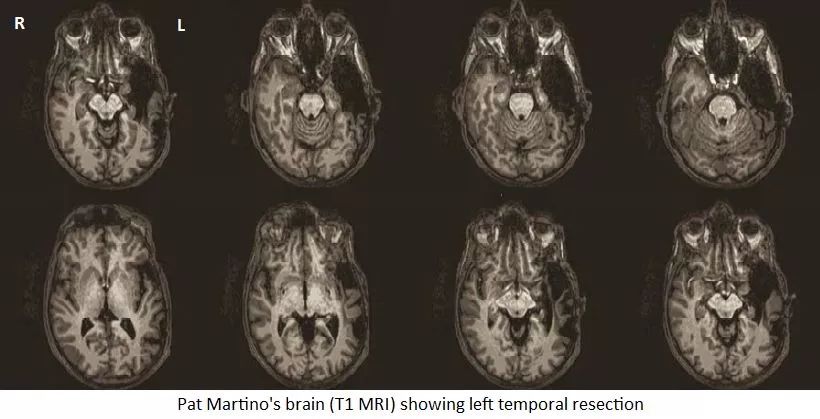

8 年前,当神经外科医生马塞洛·加拉尔萨(Marcelo Galarza)看到吉他手派特·马蒂诺(Pat Martino)大脑磁共振(MRI)成像的那一刻,他惊呆了。加拉尔萨医生说:“无法相信他的左颞叶被摘掉了这么多。”马蒂诺 1980 年动了脑部手术,移除了一团畸形的血管和动脉。当时,他是爵士乐界最有名的吉他手之一;然而,很少有人知道马蒂诺身患癫痫,忍受着剧烈头痛,还有抑郁症。他被锁在精神病病房里,电击疗法让他的身体一天天衰弱下去。

2007 年马蒂诺接受了第一次磁共振检查,直到最近几年,神经科学家才发表了基于他检查结果图像的研究。马蒂诺居然能从一场移除了相当一部分脑组织并导致失忆的手术中恢复过来,吉他技巧还与以前一样出色,这让医学专家们和马蒂诺的粉丝们都感到震惊。在 2014 年发布的一份《世界神经外科》(World Neurosurgery)报告中,来自西班牙穆尔西亚大学附属医院的加拉尔萨,和来自欧洲、美国的同事们一起写道:“就我们所知,这一案例研究是有史以来第一次观察到病人完全从长期失忆症中恢复,并且找回了自己手术前的艺术专业能力。

可以清晰地看到术后马蒂诺左颞叶的大部分已经被切除。图源:discovermagazine

手术分为两个阶段:第一步,医生移除已经形成的血块。然后,他们实施脑部血管造影术,使染色剂进入大脑流动的血液中,在 X 光照射的照射下,医生就能看到哪一部分大脑必须切除。为了移除“那一团虫子”,西蒙尼医生切除了马蒂诺左颞叶的 70% 。